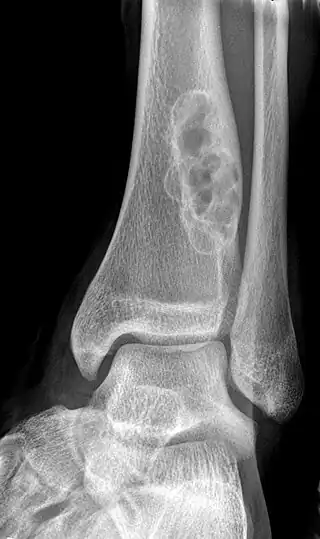

| X-ray of nonossifying fibroma of distal tibia. | |

Diagnosis is by X-ray or MRI, usually when investigating a person for something else.[3] Medical imaging typically shows a well marginated radiolucent lesion, with a distinct multilocular appearance, sometimes looking like bubbles.[3] It is usually around 1-2cm in size, but be as large as 7cm.[4] They consist of foci consist of collagen rich connective tissue, fibroblasts, histiocytes and osteoclasts.[3] Usually no treatment is required.[4] Surgical curettage and bone grafting may be required if it is large.[4]

It is usually iagnosed by x-ray or MRI, when investigating another problem.[1] The tumor presents as a well defined radiolucent lesion, with a distinct multilocular appearance, sometimes looking like a "soap bubble".[2] If small and no symptoms, then biopsy is not needed.[1]

1. a. Front view X-ray: NOF of the lower leg bone near ankle, with well-defined tumor

1. b. Side view X-ray: NOF of the lower leg bone near ankle, with well-defined tumor